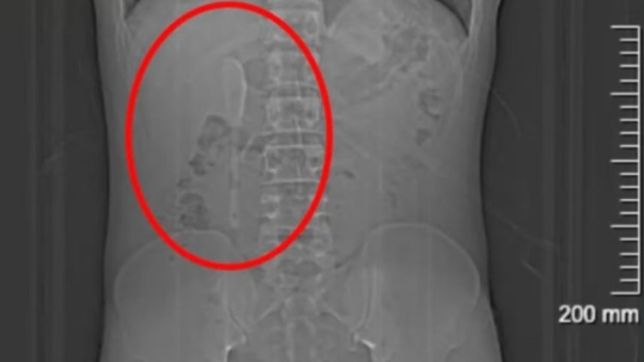

O objeto foi encontrado no estomâgo do homem após ele ser submetido a uma radiografia. Ele foi preso pela Polícia Civil de Minas Gerais

Ele foi levado para o Hospital Odilon Behrens, no bairro São Cristóvão, onde foi submetido a uma radiografia que possibilitou a constatação do acessório de ouro no estômago do suspeito.